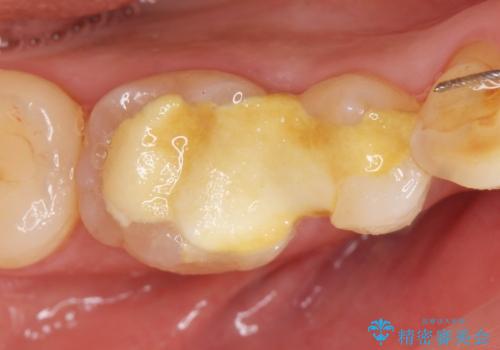

治療途中の歯 セラミック治療を希望され来院